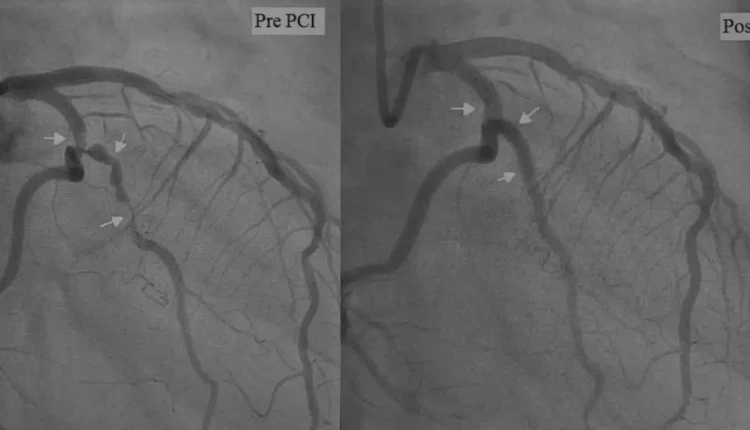

Stent, tıkalı ya da daralmış kalp damarlarının içine yerleştirilen metalik, tel kafes şeklinde küçük bir tüptür. Bu tüp, damarı açık tutarak kanın serbestçe akmasını sağlar. Genellikle anjiyo sırasında tespit edilen damar daralmasına anında müdahale edilerek takılır.

Her ne kadar stent uygulaması başarılı olsa da bazı hastalarda damar tekrar tıkanabilir. Bu durumda yeniden anjiyo yapılır. Eğer yeniden stent takılması mümkün değilse veya tıkanıklık çok yaygınsa, bypass ameliyatı önerilebilir.